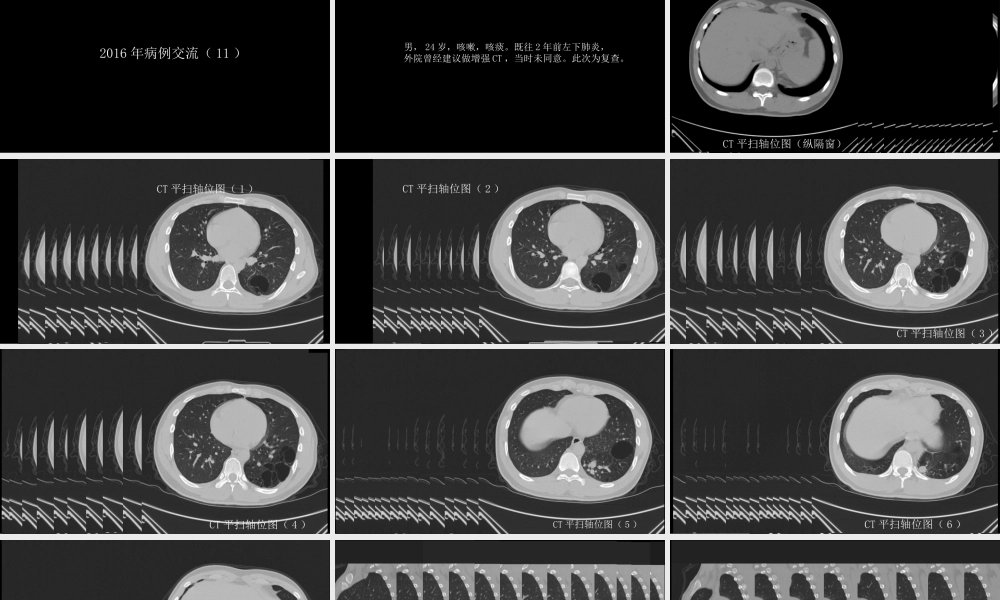

这样的肺隔离症:影像共享中国石油中心医院影像科杨景震注:请使用放映模式浏览2016年病例交流(11)男,24岁,咳嗽,咳痰。既往2年前左下肺炎,外院曾经建议做增强CT,当时未同意。此次为复查。CT平扫轴位图(纵隔窗)CT平扫轴位图(1)CT平扫轴位图(2)CT平扫轴位图(3)CT平扫轴位图(4)CT平扫轴位图(5)CT平扫轴位图(6)CT平扫轴位图(7)CT平扫矢状重组图(后基底段病变区)CT平扫矢状重组图(异常血管)冠状位重组图(后份)冠状位重组图(前份)CTA轴位图(1)CTA轴位图(2)CTA轴位图(3)CTA轴位图(4)肺部CTA斜矢状重组图CTA容积重建图本例典型的肺隔离症,伴右肺下叶发育不良。除粗大的发自主动脉的粗大异常血管外,还可见增粗的引流静脉,于三维重建图显示最直观。鉴别诊断“体循环血管供应肺”,本病不存在肺部的病变(隔离肺的囊性或块状灶),多伴有病变区肺动脉发育差。男,37岁。咳血,其他无特殊症状。增强扫描:左下肺GGO、体循环血管增多男,34岁。无明显临床症状。看到主动脉发出的异常动脉血管供应肺,不全都是肺隔离症;虽然是属于一种发育变异,但是否看作是“定时炸弹”——大咳血危险因素?复习文献中的经典病例后,你将会重视这种情况K.Tokunaga,etalECR2015EducationalExhibitPulmonaryvascularanomaliesinadult;apictorialreview女,62岁。大咳血。胸片:心脏、气管及纵隔右移位,右肺体积缩小,右侧肺门及肺部血管细小,右肺中野侵润。与左侧对比,右侧没有正常的肺纹理结构、形态!增强胸部CT及3D-CTA证实右肺动脉主干缺如。肺窗显示右肺体积缩小伴磨玻璃影以及双侧肺气肿。CTA显示源自支气管动脉、肋间动脉、胸廓内动脉、膈下动脉以及冠脉诸多侧枝血管供应右肺。右侧肺静脉狭窄。单侧肺动脉缺如UnilateralAbsenceofaPulmonaryArtery(UAPA)CTA显示源自支气管动脉、肋间动脉、胸廓内动脉、膈下动脉以及冠脉诸多侧枝血管供应右肺。肺通气灌注显像:右侧全肺V/Q(通气/血流)不匹配正常通气显像正常灌注显像该例UPAP一个值得注意的问题:本例的右肺看似含气的肺组织,但是它却是多余的(没有肺应有的气体交换功能);由于供应右肺的体循环血管破裂,而导致大咳血、最终死亡。对此或类似的体循环异常供血,尤其畸形血管较粗大者,一旦确诊,是否应尽早予以手术治疗?END